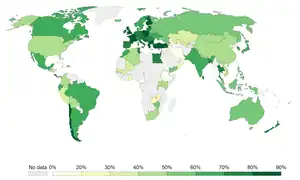

Prevention

Education and counselling by physicians of children and adolescents have been found to be effective in decreasing tobacco use.[284] The World Health Organization (WHO) estimates that 5.6 billion people, or 71% of the world's population, are protected by at least one tobacco prevention policy.[285]